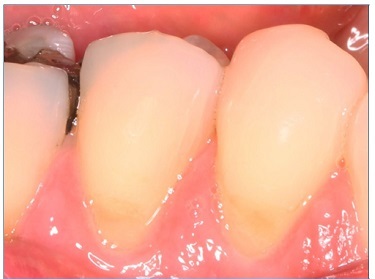

There were no dropouts in this study, so all patients were evaluated at baseline and at 6 months. Representative images of restorations are presented in Figures 1, 2, 3, 4, 5, and 6.

Figure 4 Photographs after 6 months of tooth 44’s restoration by the self‑etch technique and tooth 45’s restoration by the etch‑and‑rinse technique